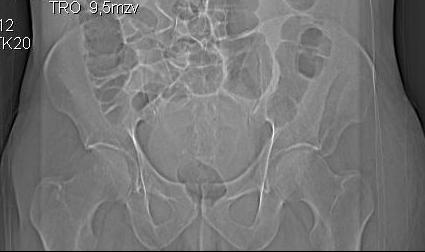

По предоставленым снимкам верифицировать повреждение невозможно.

Покажите обзорный снимок таза и проекции Judet.

Если уж делали КТ, то наверное сохранились сами срезы.